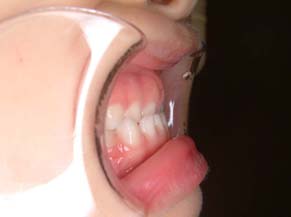

反対咬合です。